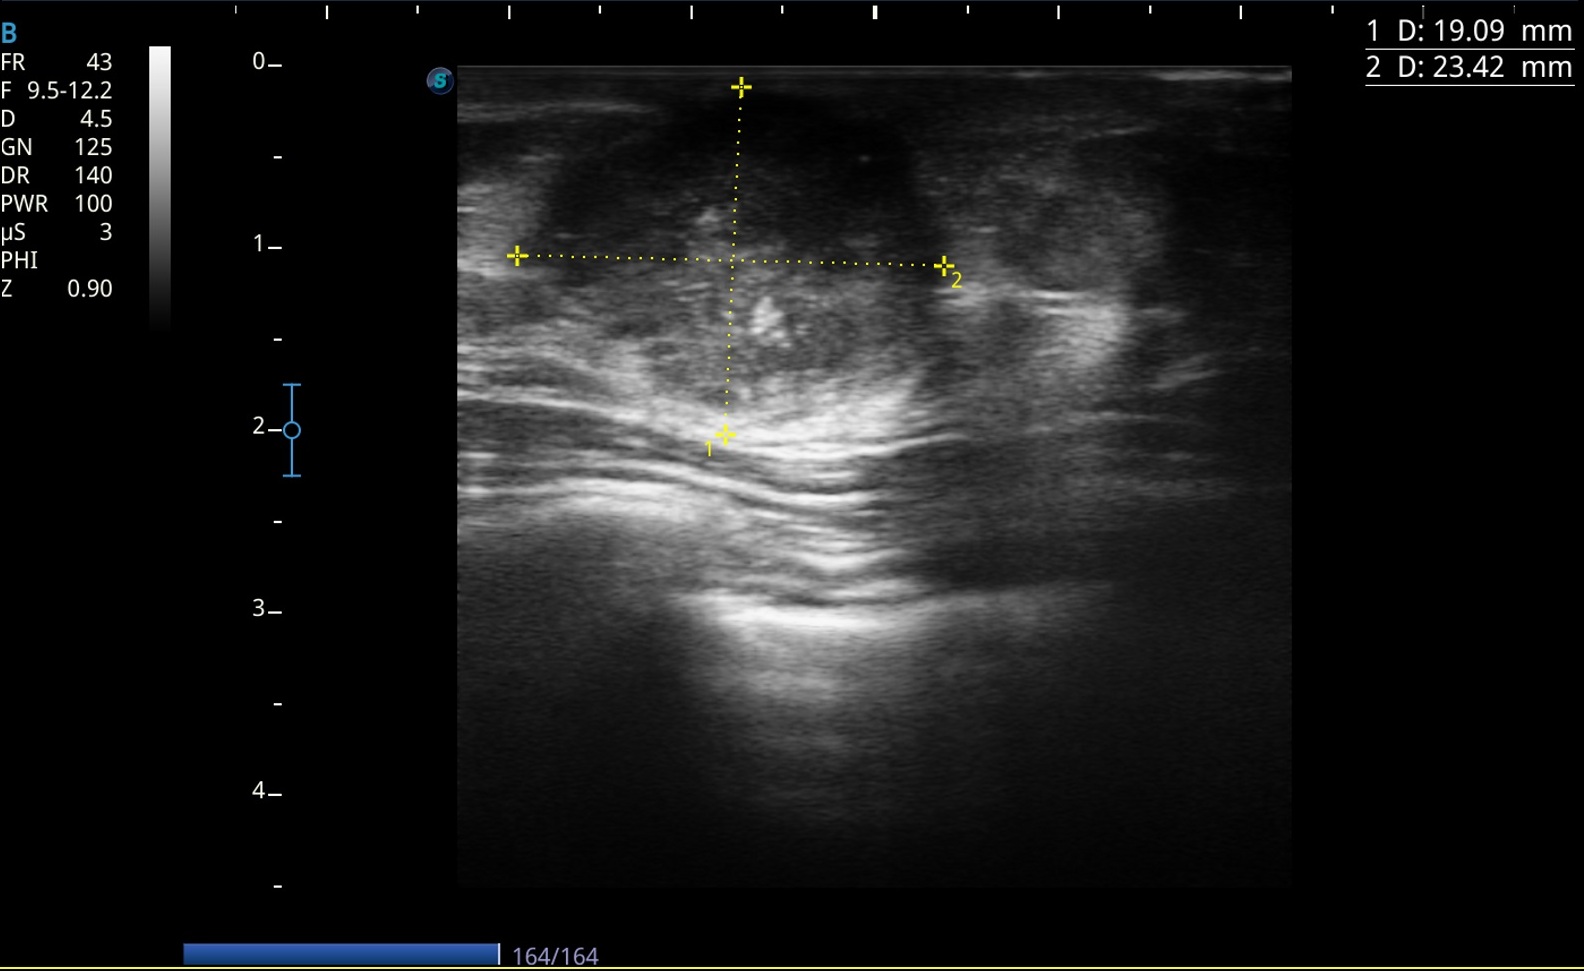

Lesión bien delimitada en cuadrante inferior externo de 4 × 1,7 cm, márgenes microlobulados, heterogénea con focos hiperecogénicos internos.